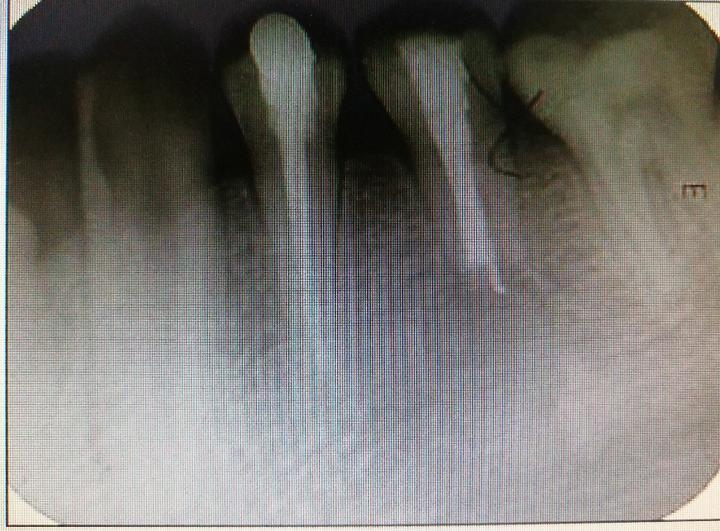

2018.3.6我接到一个网上咨询,女性患者,36岁,拍口腔全景片<strong>(图1)</strong>发现右上第五颗牙自根尖有一白线延伸,这个牙的治疗病史不祥,只记得多年前补过,经几家医院,多位线上线下医生会诊,都没能得出一致意见。归纳如下:

第一  白线为何方神圣

有说是拍片伪影的,有说是超填糊剂的,有说是超填牙胶的等等。

图1  口腔全景片示根尖白线